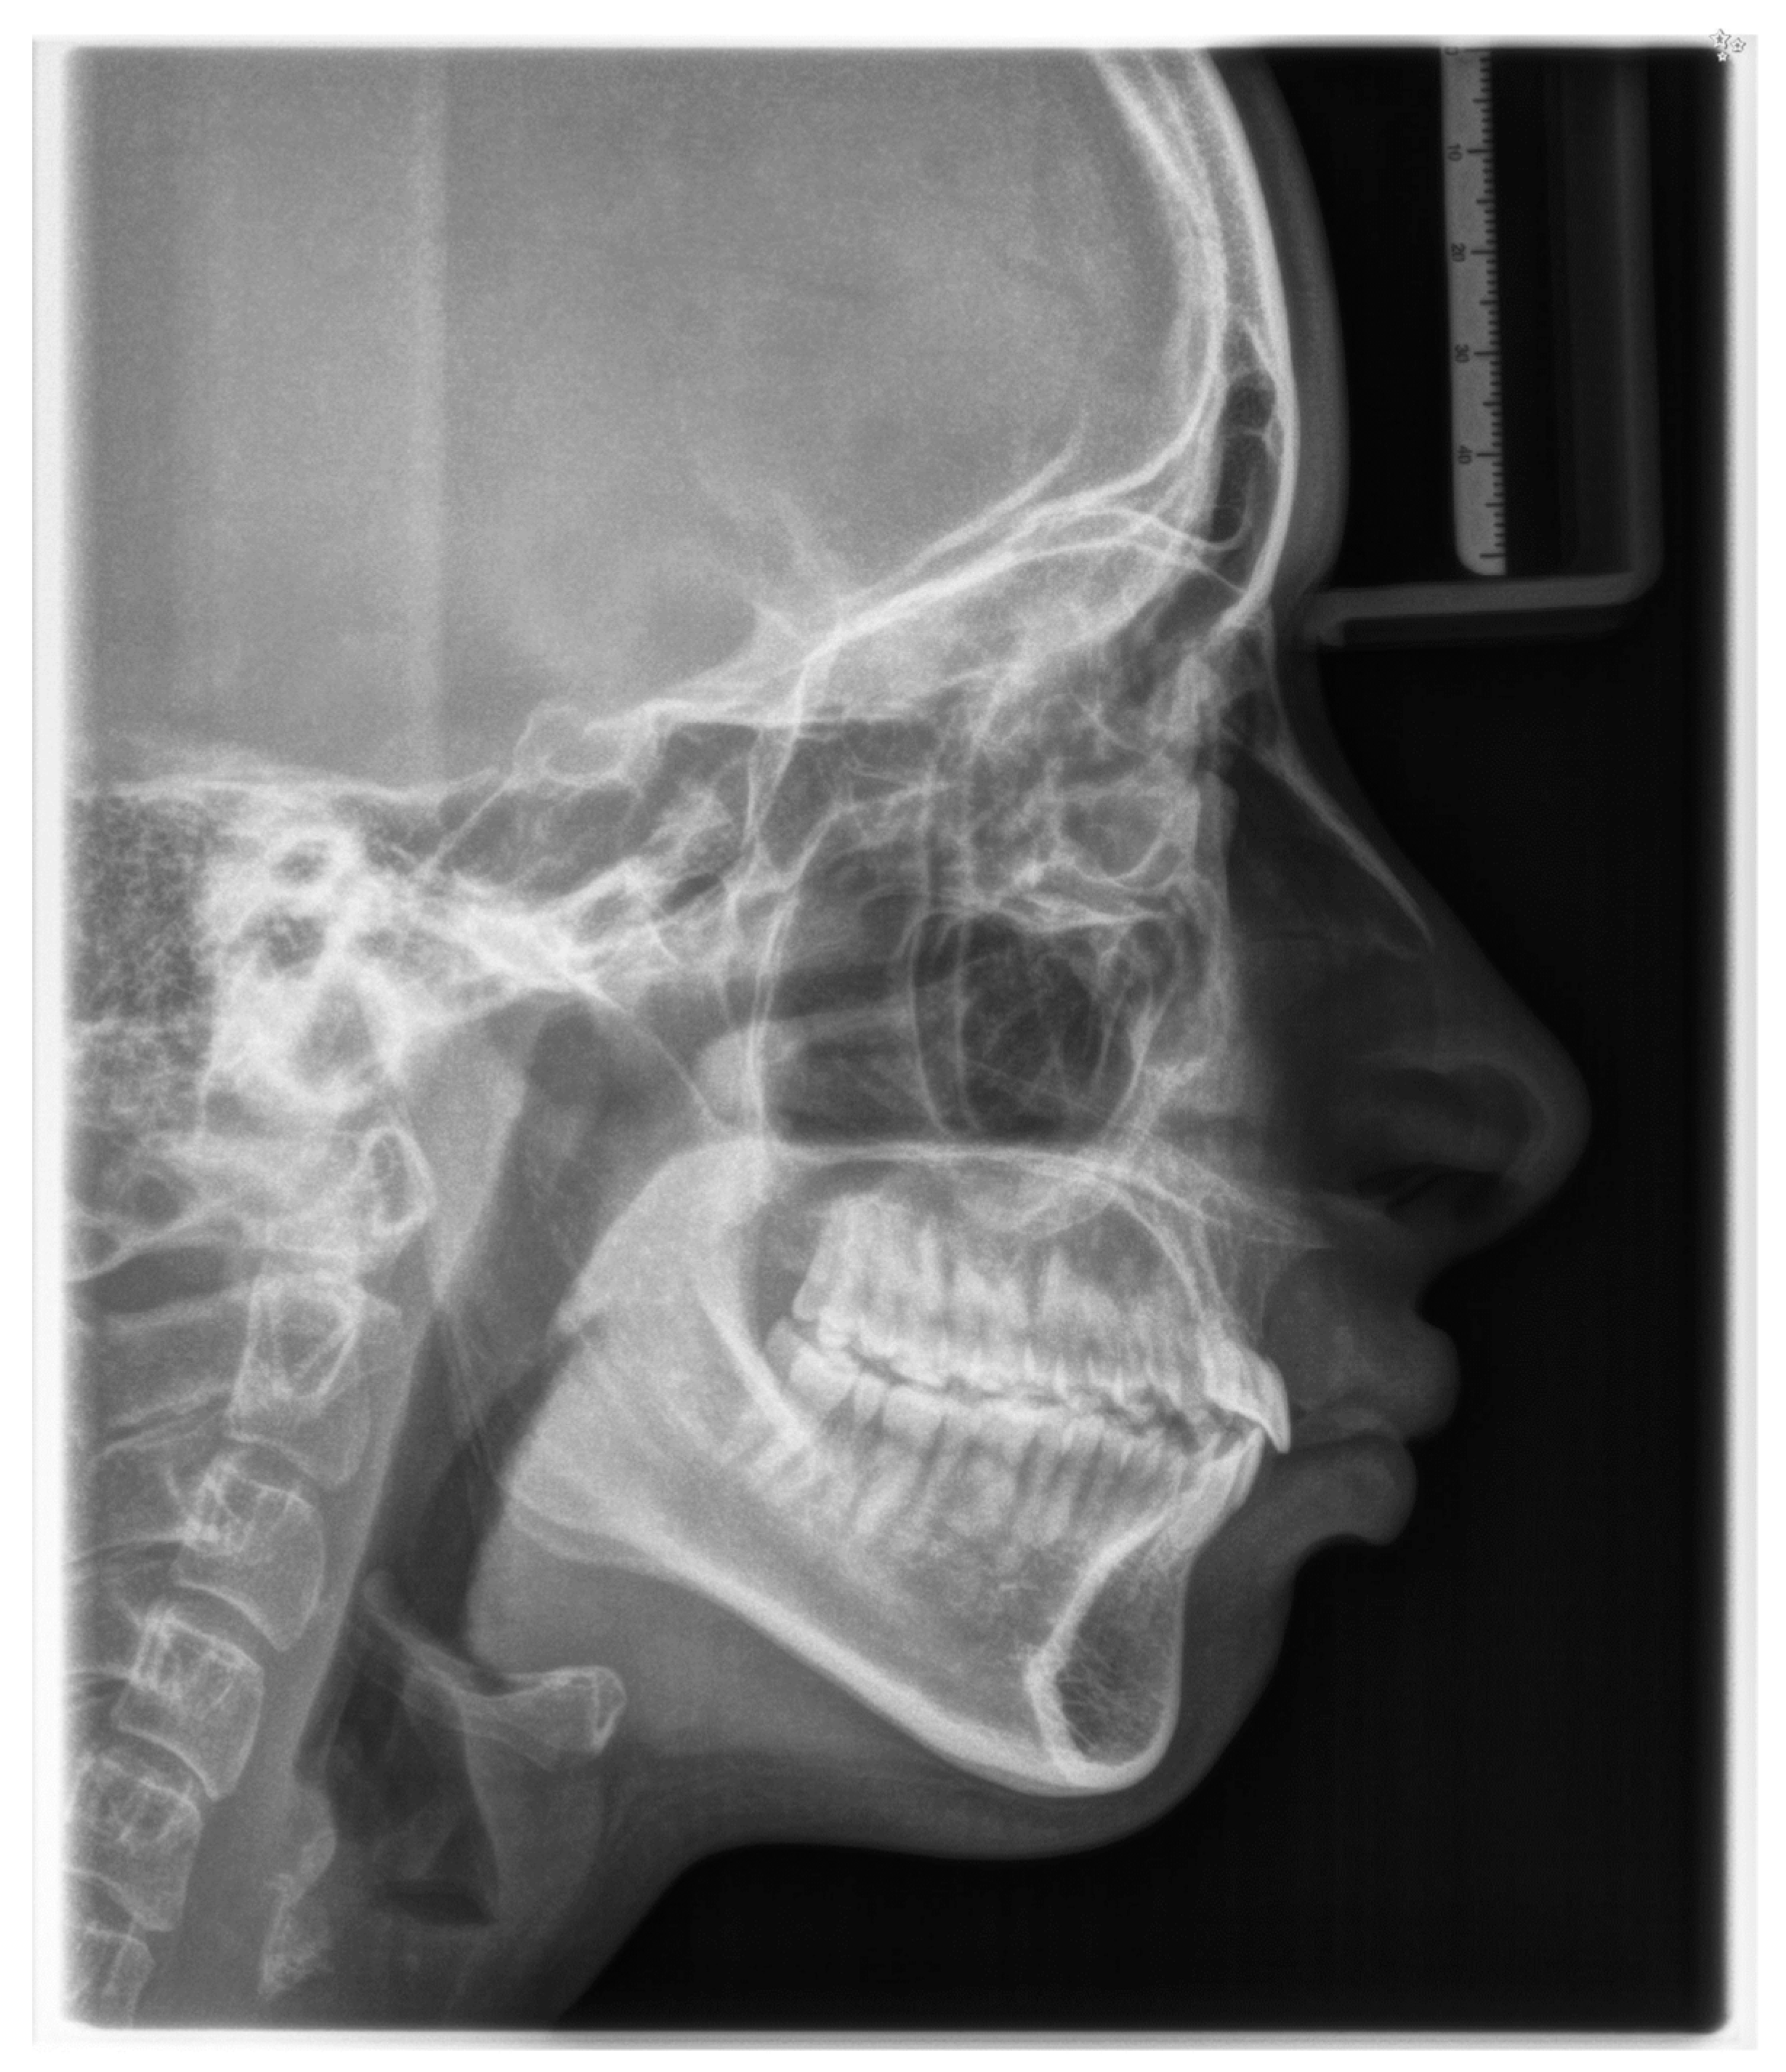

2.1. Diagnosis and Aetiology

2.2. Treatment Objectives

2.3. Treatment Progress